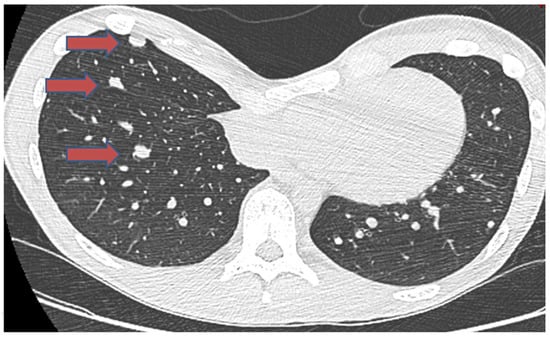

- Samargandi, R.; Bernard, M.; Miquelestorena-Standley, E.; Le Nail, L.R. Efficacy of denosumab treatment for lung metastasis secondary to proximal humerus chondroblastoma. Saudi Med. J. 2024, 45, 633. [Google Scholar] [CrossRef]

| Samargandi. [93] | 19/M | Proximal humerus | Lung, shoulder metastasis to lung | Late metastasis without local recurrence | Benign | 1 year 3 months | 2 years | Alive at last follow-up | Partial metastasectomy and denosumab |